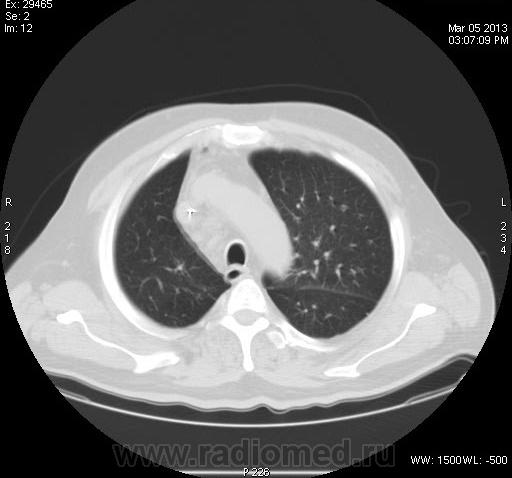

Задыхается, кашляет, Т-37, КТ "Cito!", рентгенограмм нет. В поликлинике закл.:" Двухстороння пневмония, МТС?"

Анализ изображений КТ исследования ОГК обязательно должен проводиться в двух окнах (легочном и медиастинальном). А в диф. плане, так еще  и с контрастированием. Есть ли возможность хотя бы увидеть изображения во втором режиме: для оценки участков консолидации, наличия кавтации, оценки л/узлов и средостения в целом...?

зон консолидации и лимфоузлы средостения. Похоже на саркоидоз. Тогда у  пациента не должно быть особых жалоб.

Не повезло больному. 11.03.2013г. умер в реанимации, сегодня только узнал. Причина смерти- множественные инфарт- пневмонии?!. Завтра выложу все, что найду. Я в шокеsurprise! Писал диссеминацию по типу септической + БАР.

Что говорить о контрастном КТ исследовании, если даже КТ-изображения данного пациента не выставлены во втором (медиастинальном) окне; была бы возможность оценки характера участков конолидации легочной ткани, состояния лимфатических узлов и средостения в целом.  Почему то никто не отметил наличие катеторов в верхней полой вене и правом желудочке сердца, что косвенно должно было навести на тромбоэмболический процесс. Конечно, в данном случае, КТ исследование с болюсным контрастированием помогло бы в правильной диагностике.